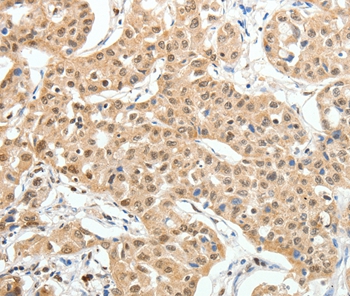

分类: 科研抗体货号: P42786别名: CIS3; SSI3; ATOD4; Cish3; SSI-3; SOCS-3应用: WB,IHC反应种属: Human,Mouse